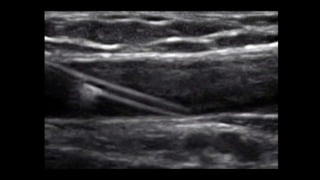

The document provides essential tips for vascular access using ultrasound, emphasizing the need for longer IV catheters to increase success rates. It suggests scanning for the largest and most superficial veins while being cautious of the free wall. Additionally, it highlights the importance of proper patient and machine positioning for optimal ergonomics and comfort during the procedure.